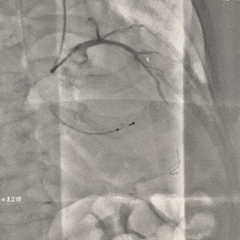

左冠提前预埋冠脉导丝

根部造影

可见明显反流,瓣叶活动度不佳

导丝顺利跨瓣

20mm球囊预扩

无腰无漏,右冠显影正常;RN侧钙化融合推挤球囊贴靠左窦侧,可见左冠显影欠佳,考虑有球囊贴靠STJ的原因,决定预埋支架保护再准备瓣膜释放